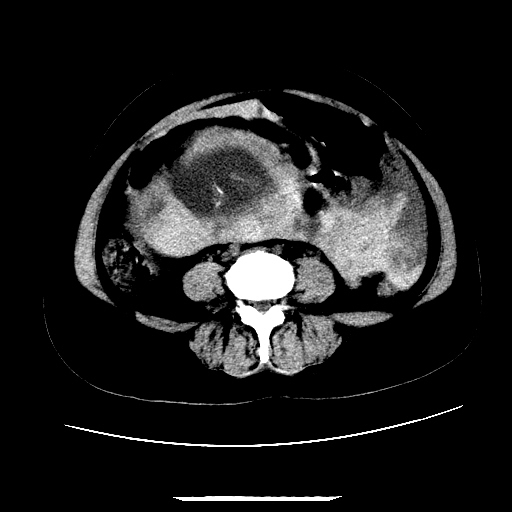

f,45y.怀孕4月晕倒,b超提示死胎,有手术结果,请展开讨论后明天告诉。

膈下-肠间隙内见气体密度影,子宫轮廓显示不清,宫腔-腹腔积液,首选考虑---子宫破裂出血。

1)宫腔妊娠。2)子宫破裂出血,腹腔及盆腔积血。

怀孕4个月晕倒,病史就这么简单?有没有腹痛呢?腹腔内有没有气体?窗宽太窄了脂肪组织与气体已不好分。如果有气体,那就是空腔脏器穿孔,如胃肠穿孔。如没有气体,就考虑子宫破裂或宫外孕破裂。正常怀孕子宫破裂很少见,有可能是宫外孕。极有可能是残角子宫怀孕破裂。腹腔怀孕破裂也有可能。

感谢同行们的高见。手术结果:子宫破裂出血。

我们的诊断是:腹、盆腔积液(考虑腹盆腔脏器破裂出血);宫腔妊娠。让人纳闷的是当时我们没有经验,现在回头看看分析:4月宫腔妊娠:1、洋膜囊不可能紧贴胎体这么小;2仔细看看子宫后壁肌层模糊不清;3腹、盆腔液体来源原因?4、45岁高龄妊娠有晕倒。由此可大胆诊断:宫腔妊娠子宫破裂出血。